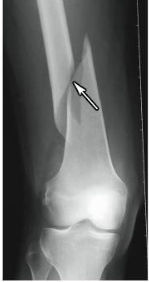

transverse fracture